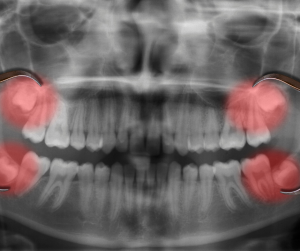

La aparición de las muelas del juicio

Un acontecimiento importante que generalmente tiene lugar entre las edades de 17 y 21 años es la aparición de los terceros molares. Tradicionalmente, se las